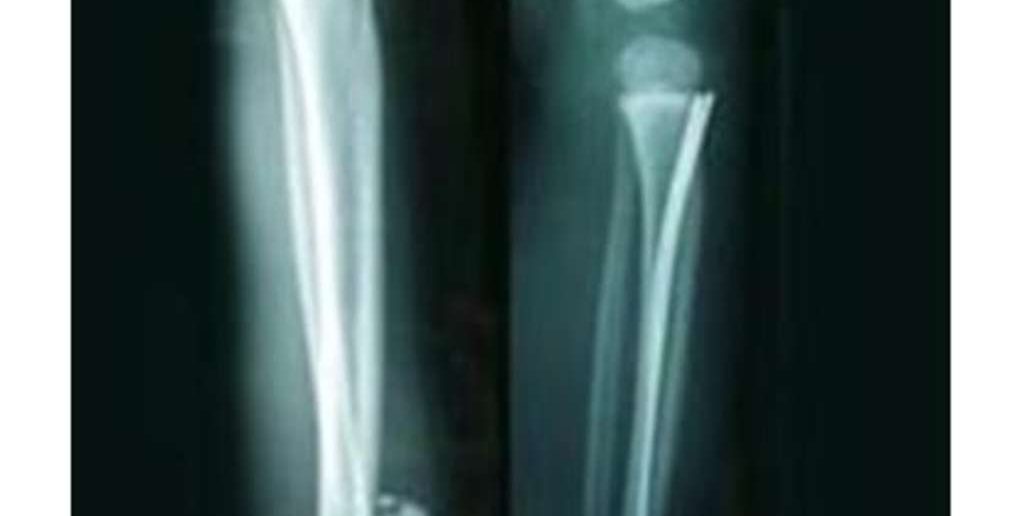

Meist genügt ein Röntgen, um den genauen Bruchverlauf zu lokalisieren. Allerdings muss auch das umliegende Gewebe der Tibia beurteilt werden. Bei möglichen Gefäßschäden sollte dann eine Röntgenuntersuchung mit Kontrastmittel (Angiographie) oder ein spezielles Ultraschall (Doppler-Sonografie) durchgeführt werden.

- Bei der OP werden die einzelnen Knochenteile mit Metallosteosynthesen (Schrauben, Platten, Marknagel, Fixateur extern) reponiert.